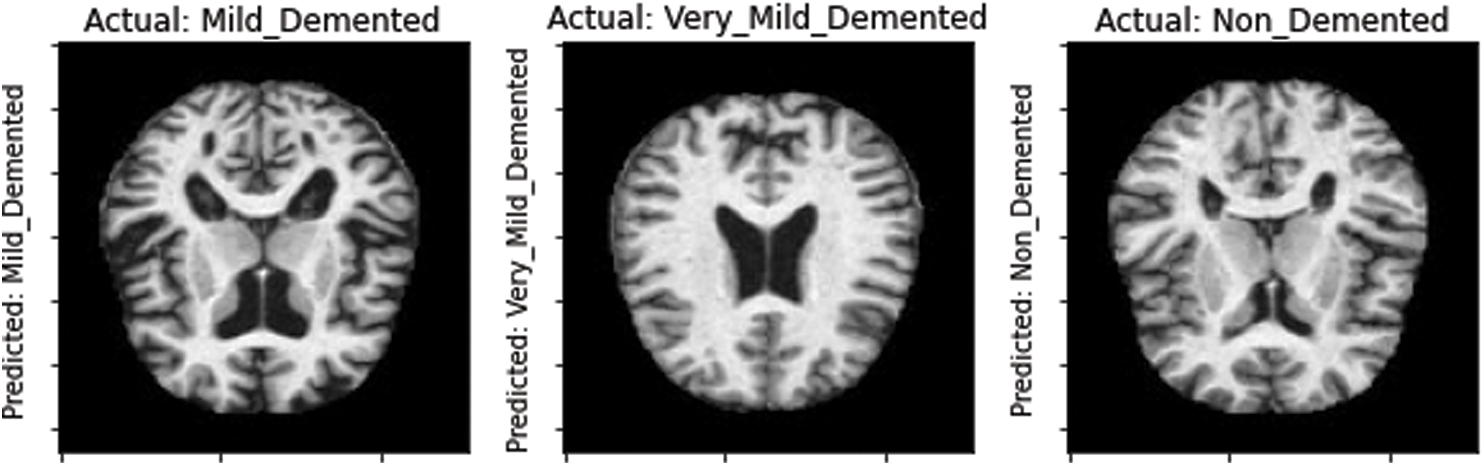

Moreover, the proposed model was tested on the unseen MRI images of the test set and achieved promising results, as shown in Fig. 8. Our proposed model predicted the same brain MRI images of Alzheimer’s patients with respect to classes that actually belong to those classes. This also leads us to conclude that our proposed model is reliable for detecting AD stages and can be used as a medical decision support system that helps physicians in their diagnosing tasks.

Figure 8: Model-predicted results